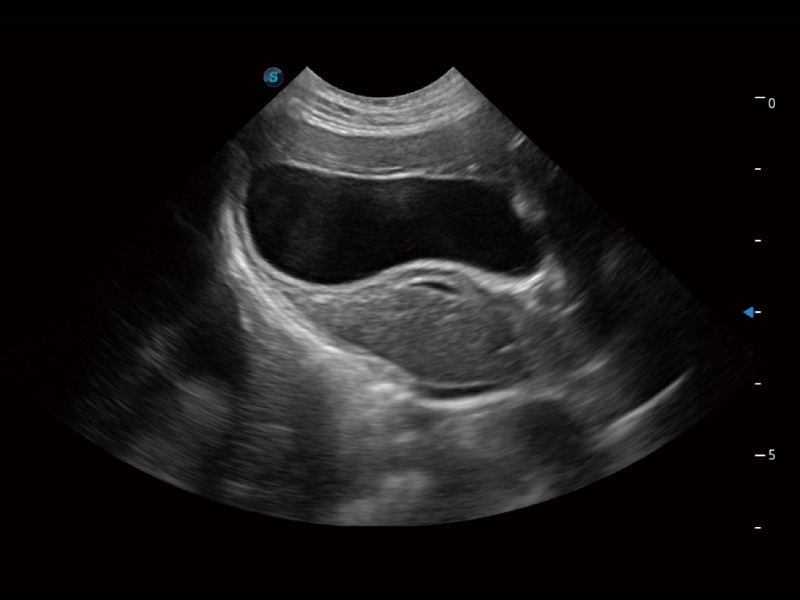

一鍵自動識別膀胱壁及自動測量膀胱容積,不受膀胱形狀和大小的限制,幫助醫(yī)生快速精準(zhǔn)獲得測量的數(shù)據(jù)。

ProPet 70專為動物醫(yī)生設(shè)計(jì),對不同的動物體型和生理結(jié)構(gòu)作出了針對性的優(yōu)化。通過動物影像專用軟件,可滿足個性化的應(yīng)用需求,幫助動物醫(yī)生獲得更精確的診斷數(shù)據(jù)。

為精細(xì)結(jié)構(gòu)及組織邊緣提供高清晰度的圖像和更大的成像視野。幫助減輕醫(yī)生的用眼疲勞,快速精準(zhǔn)獲得測量的數(shù)據(jù)。